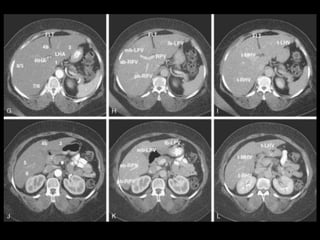

Subdivisão Funcional

• Alem de anatômico, os lobos direito e

esquerdos são divididos funcionalmente.

– Cada um recebe sua tronco primário da artéria

hepática, tem sua própria veia portal e drena para

o seu próprio ducto hepático.

• Caudado também funciona separadamente.

– “Terceiro fígado”

• Depois pode ser divido em 4 partes e 8

segmentos ressecáveis cirurgicamente.

Subdivisão Funcional • Alemde anatômico, os lobos direito e esquerdos são divididos funcionalmente. – Cada um recebe sua tronco primário da artéria hepática, tem sua própria veia portal e drena para o seu próprio ducto hepático. • Caudado também funciona separadamente. – “Terceiro fígado” • Depois pode ser divido em 4 partes e 8 segmentos ressecáveis cirurgicamente.

Subdivisão Funcional • Osoito segmentos são divididos: – A primeira divisão é realizada dividindo através da Porta Hepática, em esquerdo (I a IV) e direito (V a VIII) – A divisão é feita baseada em um relógio – Caudado é o segmento I – No ‘lobo’ esquerdo, o IV separa-se do II e do III pela veia hepática esquerda, representado anatomicamente pelo ligamento falciforme. – II e III se dividem através de uma linha imaginária transversal na altura da porta hepática. – No ‘lobo’ direito, se divide os segmentos através de uma linha transversal e pela veia hepática direita.

Subdivisão Funcional • Fundamentalimportância para Ressecção. • Maioria das lesões são do fígado direito.